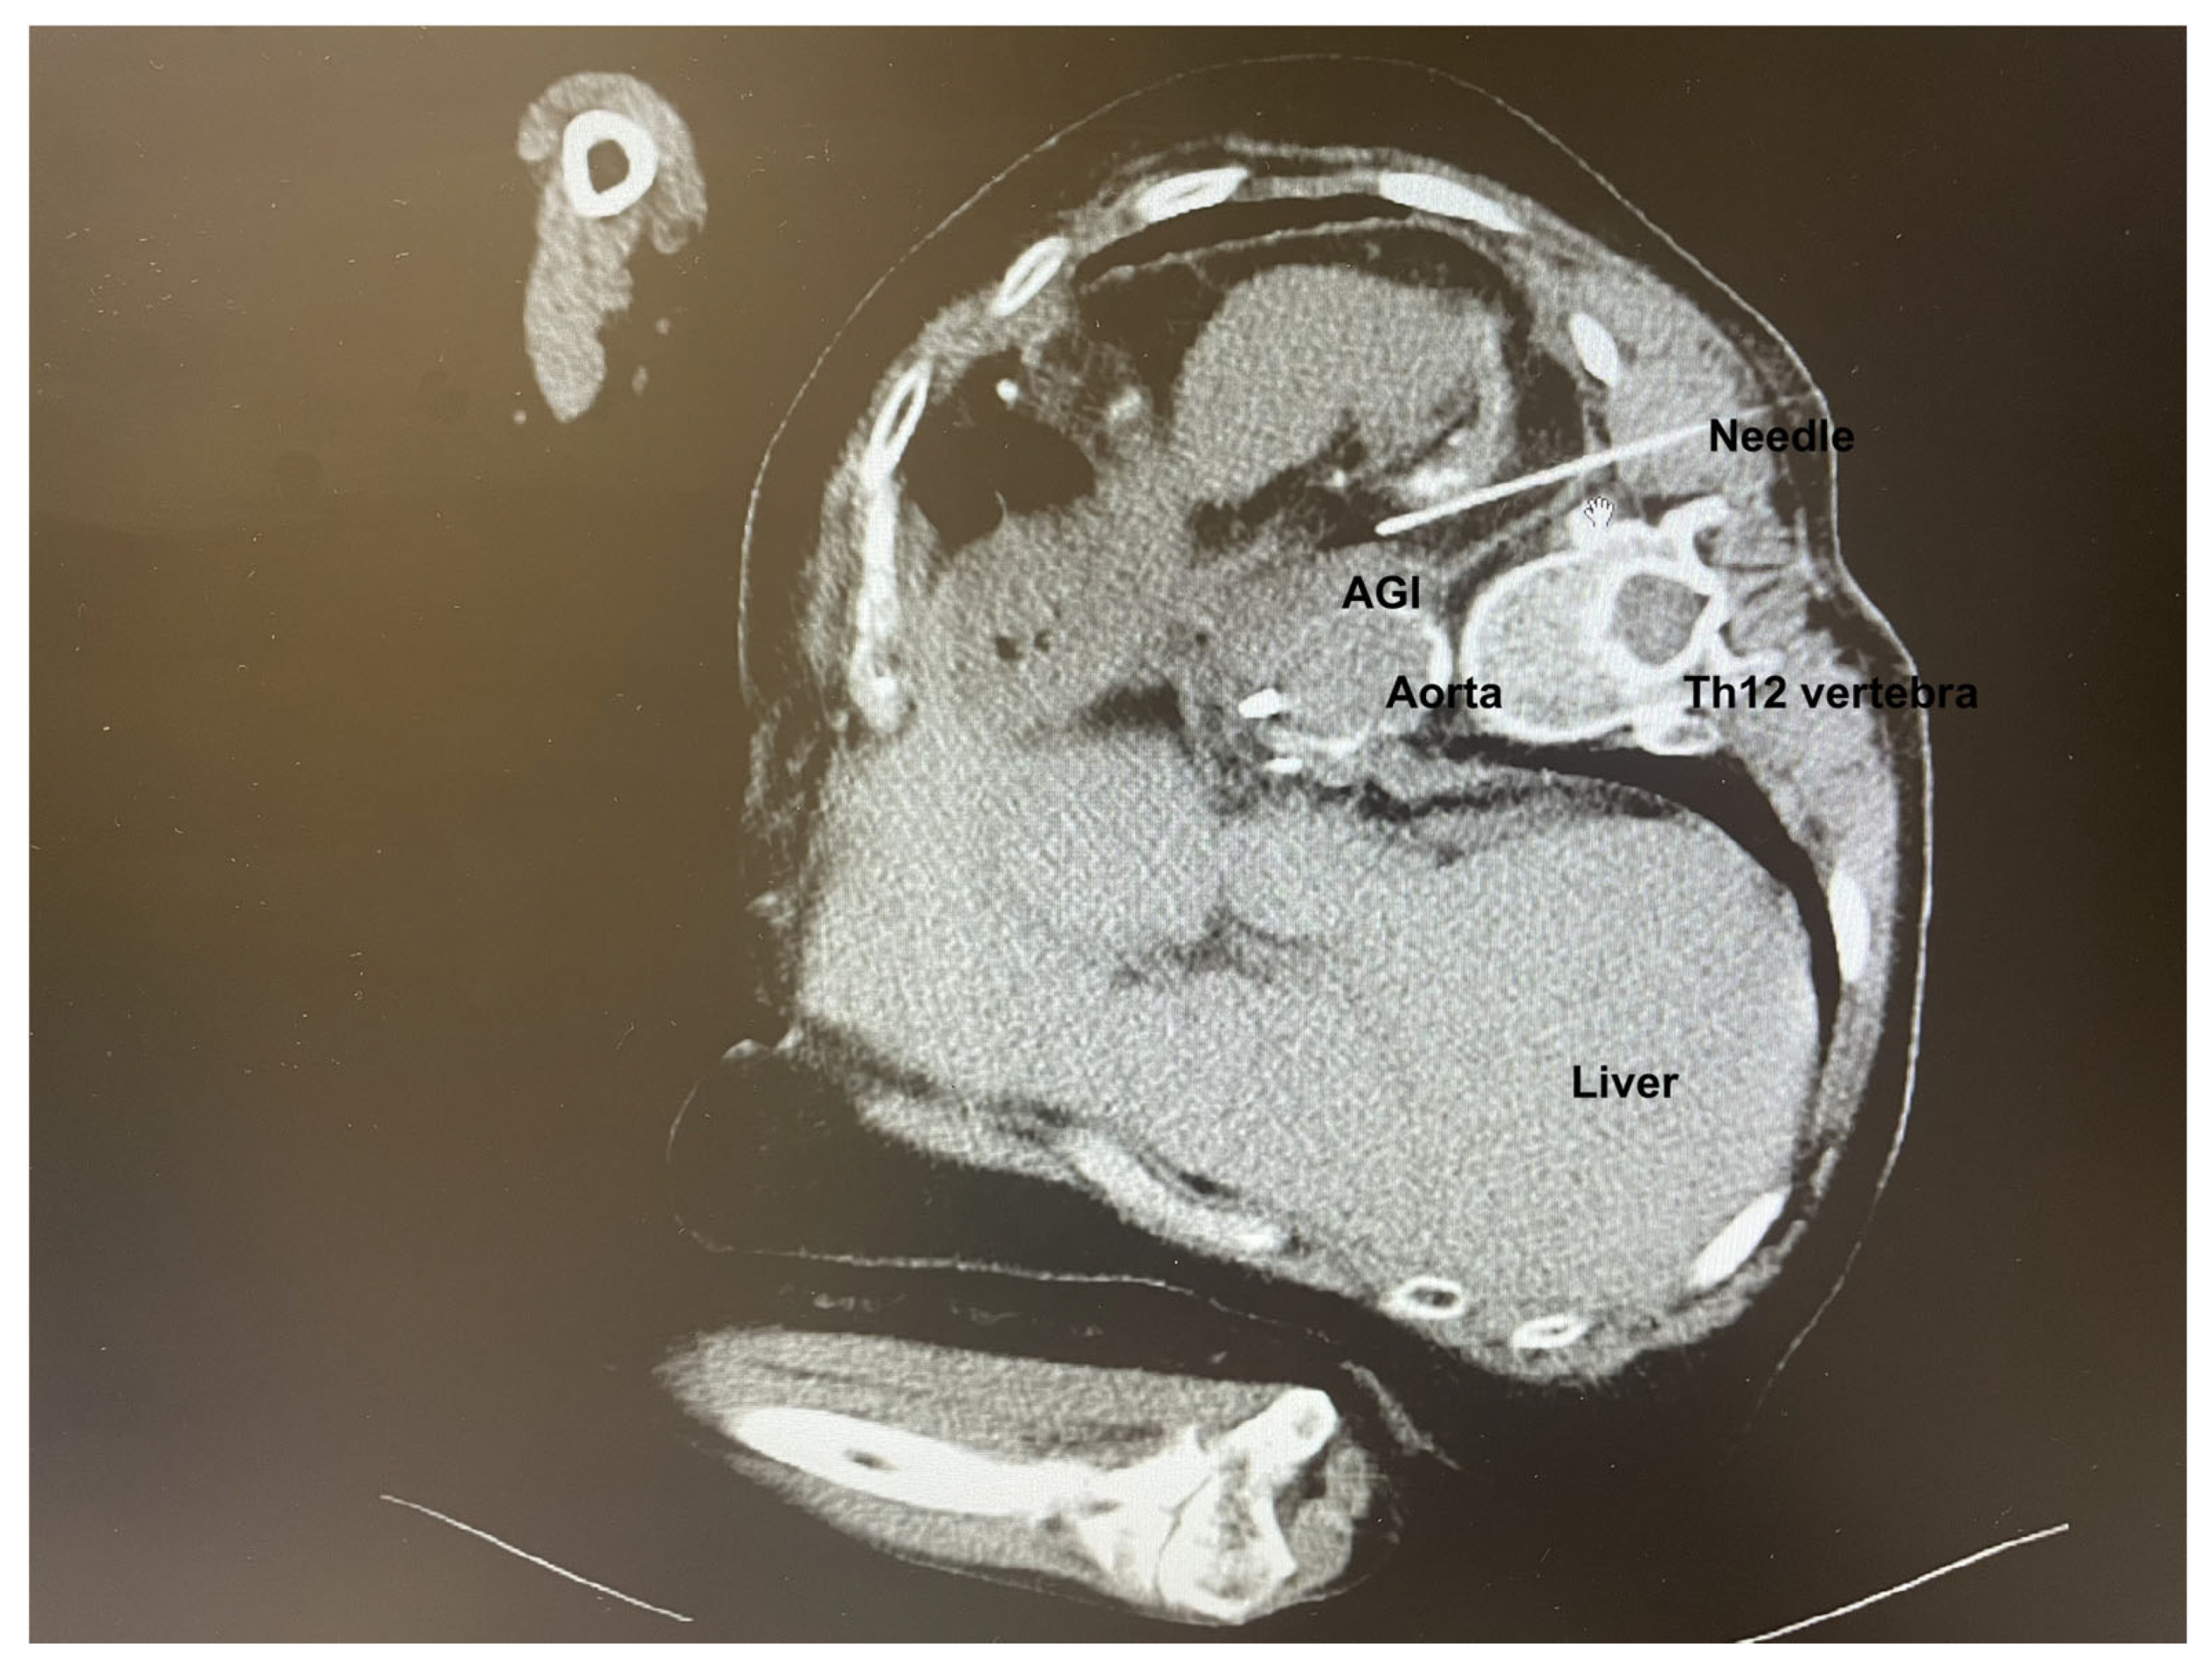

Following confirmation of an aortic graft infection (AGI), antibiotic therapy was adjusted to meropenem and linezolid. A multidisciplinary team comprising of a vascular surgeon and an interventional radiologist decided to proceed with CT-guided percutaneous drainage of the AGI (Figure 1). Due to the extremely challenging localization of the AGI, general anesthesia in the prone position was preferred to enhance the safety of the procedure, to minimize patient discomfort, and prevent unintended movement during the procedure.

Throughout the procedure, the patient remained sedated, comfortable, and free of unwanted movements, with oxygen saturation between 92 and 96%. The interventional radiologist infiltrated the skin with 2% lidocaine and successfully performed the puncture through the left paravertebral space of the 12th thoracic vertebra. Upon puncturing the AGI, purulent material was aspirated and an 8.5 F drain with an internal locking mechanism was placed (Figure 2). The entire procedure, including preparation, lasted 105 min, with the sedation for the CT-guided percutaneous drainage lasting 65 min. The process was uneventful, with stable vital signs throughout the whole procedure. No adverse events such as hypotension, bradycardia, or respiratory depression were observed.

Figure 1. CT-guided percutaneous drainage of AGI. The patient is in the right lateral decubital position. The left paravertebral space of the 12th thoracic vertebra is the site of the puncture.